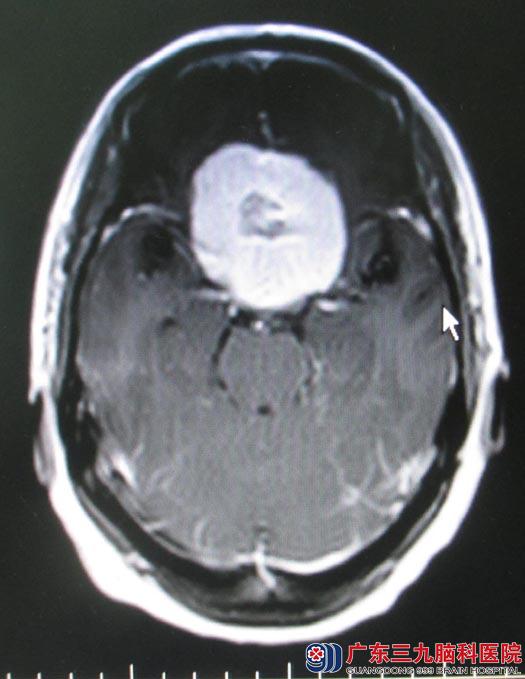

一周前视力下降逐渐加重,当地医院双侧视力及视野检查提示“双眼颞侧视野明显下降”,随后头颅MRI检查提示“前颅窝底占位,直径约5cm,考虑脑膜瘤”;广东三九脑科医院头颅MRI检查结果:前颅窝底占位,直径约5cm,考虑脑膜瘤。

由于肿瘤基底部位于蝶骨平台,往后压迫视交叉,包绕并向后外侧挤压双侧颈内动脉,手术中如何保护颈内动脉及其分支,减少对垂体柄、视神经、下丘脑等重要结构的损伤成为手术的难点。